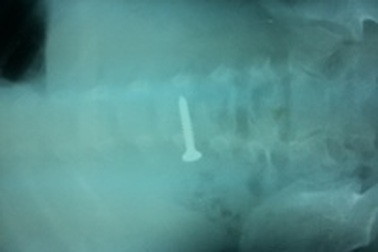

Đinh vít chui tọt vào dạ dày bé trai 11 tháng tuổiNgay sau khi phát hiện con trai 11 tháng tuổi nuốt dị vật là một chiếc đinh vít dài, gia đình vội đưa trẻ đến Trung tâm y tế huyện Tiên Yên, tỉnh Quảng Ninh khám cấp cứu.

Quảng Bình: Bé 3 tuổi nuốt đinh vít vào bụngChiều 15/7, các bác sĩ Bệnh viện Hữu nghị Việt Nam - Cu Ba Đồng Hới cho biết, bệnh viện này vừa tiếp nhận và cấp cứu bé trai V.K.T.D., (3 tuổi, ở xã Lộc Ninh, TP Đồng Hới, tỉnh Quảng Bình) do nuốt 1 chiếc đinh vít vào bụng.

Gắp thành công đinh vít bằng sắt dài 3,5 cm nằm trong tá tràng cháu béNgày 15/6, thông tin từ bệnh viện Hữu nghị đa khoa Nghệ An cho biết, đơn vị vừa gắp thành công dị vật là một chiếc đinh vít sắc nhọn dài đến 3,5 cm từ tá tràng của một bệnh nhi ra ngoài an toàn.